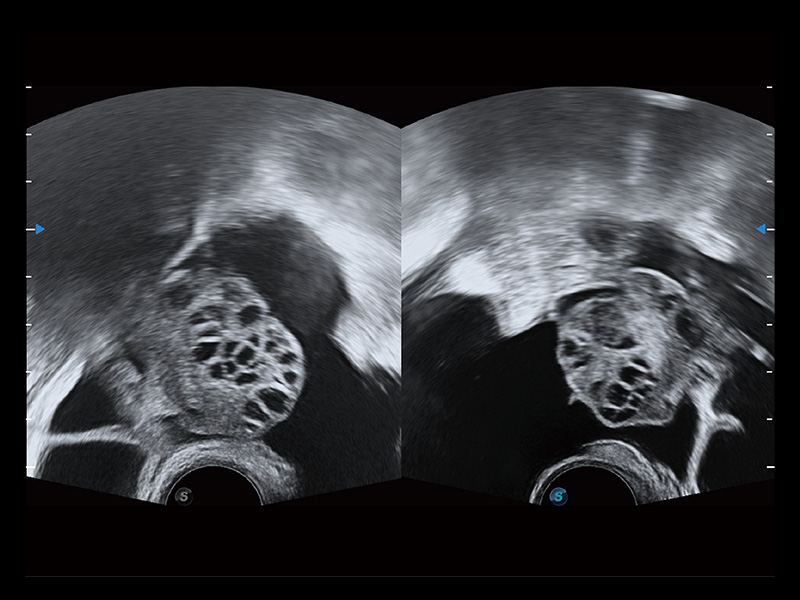

卵巢多囊样改变

中央型宫腔粘连

输卵管间质部妊娠